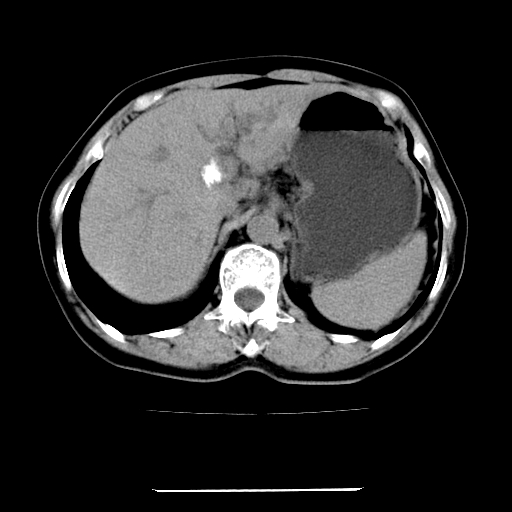

标题: CT22301:女,67岁,上腹部疼痛一周伴皮肤黄染,无发热。 [打印本页]

女,67岁,上腹部疼痛一周伴皮肤黄染,无发热。

左叶肝内胆管结石,并远端肝内胆管扩张。

考虑:肝内胆管结石继发肝内胆管扩张,右肾旋转不良。

肝内外胆管结石并肝内胆管扩张。

建议薄层观察,除外肝门部胆管细胞癌

考虑肝胆管癌;胰头占位?【形态失常,体积增大】

1、肝门高密度影下层面和胰头层面可见轻度胆管扩张,而静脉和延迟期均未见扫描完胰头,不能完全排除胰头占位。2、肝门部高密度影,考虑钙化或结石。

考虑肝门胆管癌伴门脉左支受侵包埋,建议mrcp进一步检查。